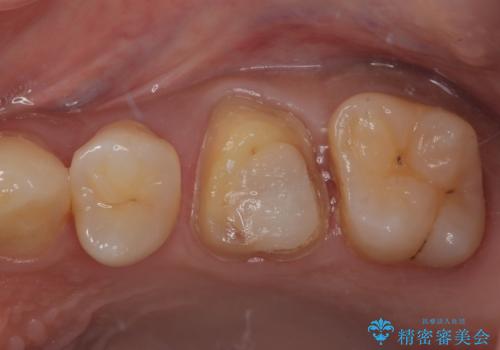

- 銀歯を外したいとのことで来院された患者様です。検査の結果、メタルインレーの範囲も大きいためオールセラミッククラウンにて補綴治療を行っていくことにしました。

拡大鏡視野下でメタルインレー、虫歯の除去を行いオールセラミッククラウンに適した形に整えました。